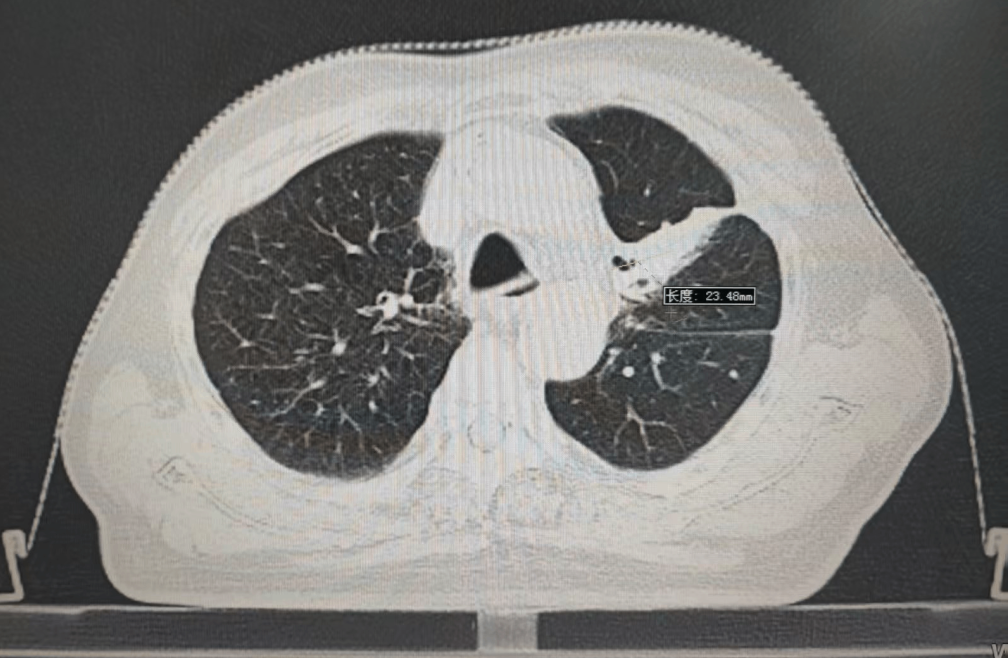

内容提要 PART. 01 高龄抗癌的“生死抉择” 当6.7cm肿瘤遇上80岁身体 四年前,李大爷因乏力、消瘦、气短等症状,意外发现左肺巨大占位,大小约6.7cm×4.9cm,最终在北京大学肿瘤医院确诊为肺鳞癌。面对82岁高龄和肿瘤的凶猛进展,家属一度陷入绝望,并决定回到家乡医院寻求治疗方法。 治疗前肿瘤影像 “开胸手术风险极高,传统化疗对肺鳞癌效果有限,还可能加重身体负担。”王春强主任回忆,团队当即决定采用局部精准放疗,在确保疗效的同时,最大限度减少对正常组织的损伤,提高生活质量,为老人开辟一条生路。 PART. 02 四年抗癌“成绩单” 肿瘤缩小70%,生活如常 治疗的关键在于“毫米级”的精准打击。依托国内顶尖放疗设备——美国瓦里安直线加速器,团队通过三维适形调强放疗技术(IMRT),将放射线误差控制在1mm内,既集中火力攻击肿瘤,又能降低周围肺组织损伤。配合PET/CT生物靶区动态追踪技术,医生能清晰区分活跃癌细胞与坏死组织,实时调整治疗方案。 四年间,李大爷的肿瘤病灶持续缩小,从最初的6.7cm缩小至目前的2.3cm,气短症状显著改善,治疗期间甚至未出现放射性肺炎等并发症。如今的他不仅生活完全自理,还活跃于社区老年活动,焦虑评分从重度降至几乎消失。 治疗后肿瘤影像 “很多患者以为抗癌就是‘你死我活’,其实‘带瘤生存’同样能创造生命价值。”这场“生命奇迹”的背后,是市二院放射治疗中心对精准医学的深刻践行,科室凭借超高的技术水平及一批国际顶尖设备支持,不断提升生物靶区勾画精度,并建立多学科诊疗(MDT)模式,融合外科、靶向、免疫、粒子等手段,为200余例高龄肿瘤患者制定个性化方案,颠覆了“高龄癌症等于绝症”的传统认知。 PART. 03 人民医院 人民名医 王春强 副主任医师 ·葫芦岛市第二人民医院放射治疗中心主任 ·原中国人民解放军第255医院放射治疗组组长 ·天津市第五中心医院放射治疗科主治医师 ·中国抗癌协会会员 ·中国医学继续教育协会肿瘤放射治疗专业委员 ·中国老年保健协会免疫健康管理专业委员会委员 ·中国老年保健协会多学科诊疗专业委员会委员 ·辽宁省免疫学会肿瘤营养与免疫分会委员会委员 专业特色: 从事肿瘤放射治疗近20年,曾于空军总医院进修肿瘤放射治疗学。擅长头颈部肿瘤、胸腹部肿瘤、盆腔肿瘤等肿瘤多发、疑难病诊治。精通三维适形放射治疗(3DCRT)、调强放射治疗(IMRT)、图像引导放射治疗(IGRT)、容积旋转调强放射治疗(Rapid-Arc)、SBRT、VMAT等先进放疗技术。尤其擅长中枢神经系统肿瘤、鼻咽癌、宫颈癌、直肠癌、食管癌、肺癌、脑转移、骨转移、淋巴结转移、肺转移、肝转移等肿瘤的放疗,尤其对部分肿瘤的疑难杂症的处理积累了丰富的经验。熟练掌握头颈部及体部肿瘤的影像诊断及综合治疗原则,注重规范化治疗。擅长为肿瘤患者制定个体化治疗方案。